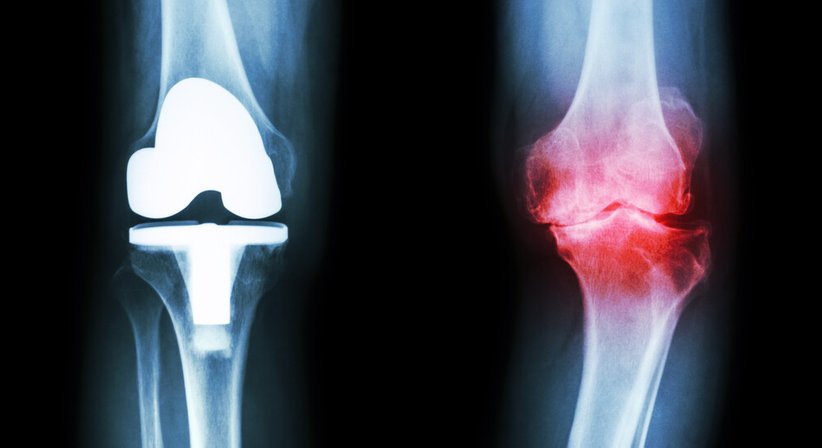

Die Gonarthrose ist eine typische Abnutzungs- bzw. Verschleißerscheinung, die sich meist langsam und schleichend entwickelt. Sie kann aufgrund bestimmter Risikofaktoren (u.a. starkes Übergewicht, Beinachsenfehlstellung, Verletzungen des Kniegelenks) auch schon bei jüngeren Menschen entstehen.

Die Behandlung einer Gonarthrose richtet sich nach dem Schweregrad der Beschwerden und kann sowohl konservativ als auch operativ (künstlicher Gelenkersatz) erfolgen.